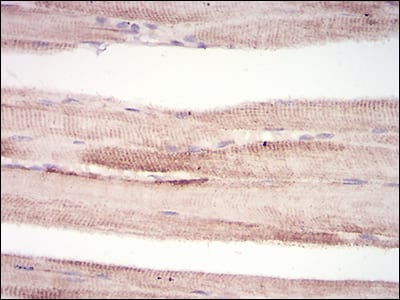

| IHC | 1/200 - 1/1000 | Human,Mouse,Rat |

MuRF1 (Muscle RING-finger protein-1) is a key E3 ubiquitin ligase involved in muscle protein degradation through the ubiquitin-proteasome system (UPS). It belongs to the TRIM protein family and is predominantly expressed in striated muscle. MuRF1 plays a central role in muscle atrophy by tagging contractile proteins, such as myosin heavy chains, for proteasomal breakdown. Its expression is upregulated under catabolic conditions like fasting, denervation, disuse, cancer cachexia, and sepsis, making it a biomarker for muscle wasting.

Antibodies targeting MuRF1 are essential tools for studying its expression, localization, and interactions in muscle pathology. They are widely used in techniques like Western blotting, immunohistochemistry, and immunoprecipitation to investigate MuRF1's regulatory mechanisms. Specificity and validation across species (human, mouse, rat) are critical due to potential cross-reactivity with other TRIM proteins. Both monoclonal and polyoclonal antibodies are available, each offering distinct advantages in sensitivity and application scope.